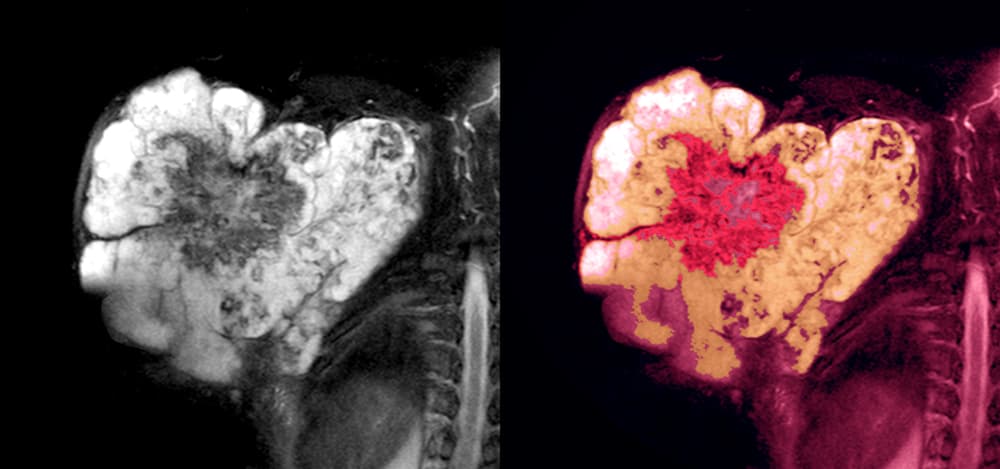

Cáncer cerebral

La gravedad y detección del cáncer cerebral depende principalmente de la parte en el cerebro donde se originen los tumores. De acuerdo con el Dr. Mark R. Gilbert existen más de 130 tipos de tumores cerebrales.

En algunos casos, estas masas malignas de células pueden estar afectando regiones del cerebro donde es más evidente el daño.

No obstante, en otras situaciones, el tumor puede estar localizado en una zona donde el síntoma más notorio sea únicamente problemas de memoria o cansancio.